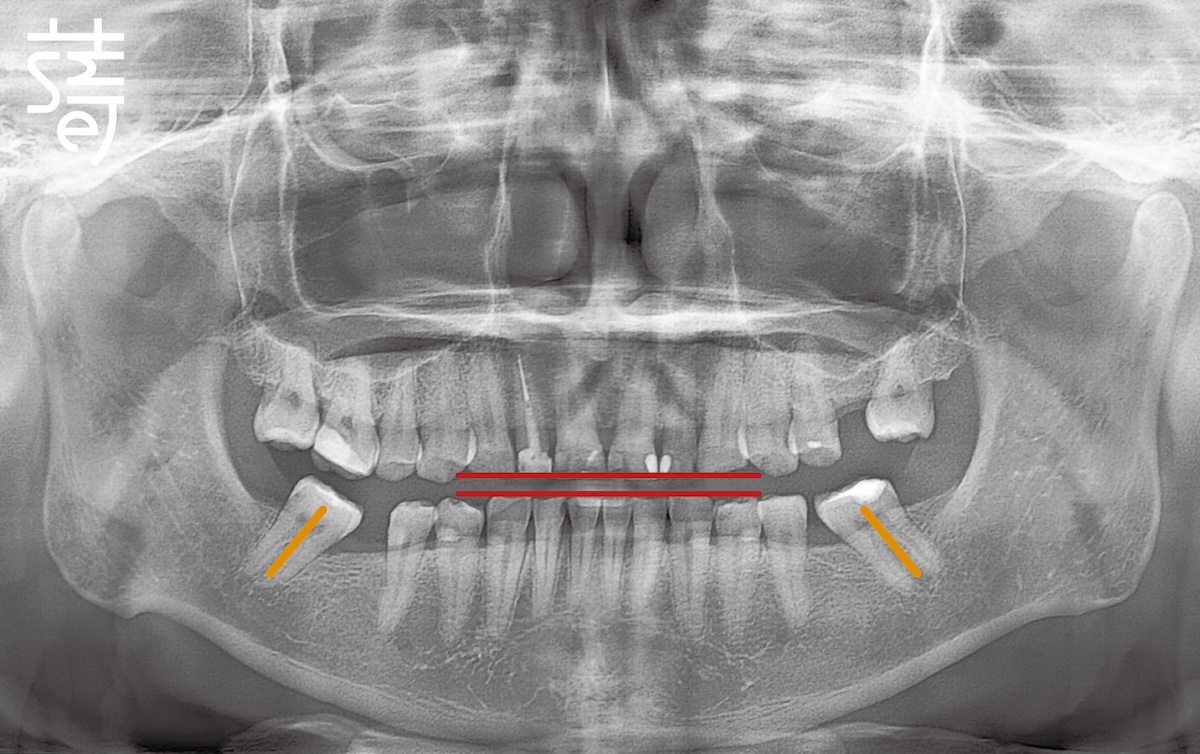

三十多歲的李先生就是典型例子。多年磨牙讓牙齒幾乎磨平,加上後牙缺失、牙齒傾倒,導致越咬越深。長期下來,不僅口腔功能受限,也讓他這位經常需要上鏡的專業人士,在鏡頭前漸漸失去自信。

Mr. Li, in his thirties, is a textbook case. Years of grinding had flattened his teeth, while missing and tilted molars worsened the bite. Over time, his oral function suffered, and as a professional frequently on camera, he gradually lost confidence in front of the lens.

將牙齒重新排列整齊,調整上下咬合,把原本傾倒的第二大臼齒推回正確位置,為後續植牙和假牙重建打好基礎。

Teeth were realigned, the bite adjusted, and the previously tilted second molars repositioned, laying a solid foundation for implants and prosthetics.

針對缺牙已久的後牙區進行植牙,恢復後牙支撐,避免整體咬合繼續崩塌,讓口腔受力更均衡。

Implants were placed in the long-missing molar areas to restore support, prevent further bite collapse, and balance oral forces.